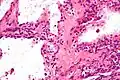

Micrograph showing a pancreatic serous cystadenoma. H&E stain.